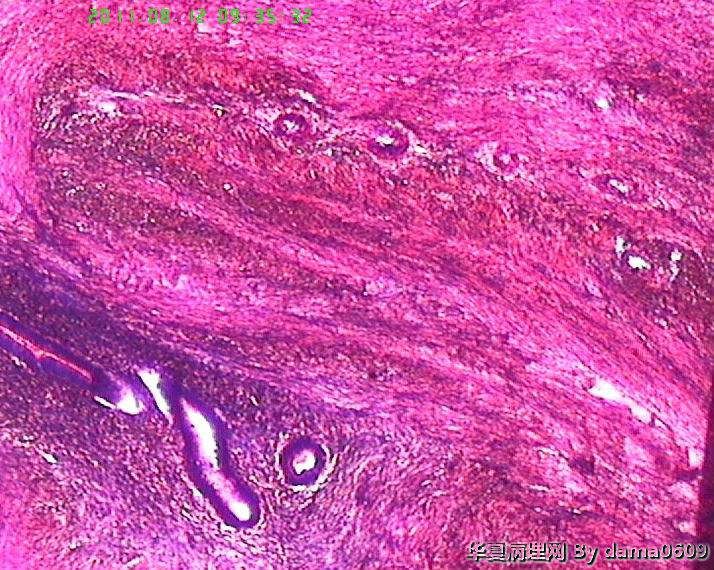

老师好!以前学生也遇到过此情况,偶尔染出的片子的细胞核的上方会出现黑色的异物,多见于子宫平滑肌瘤的片子。很影响观察核的形态、核分裂像。初以为是苏木素杂质,而且不经常出现,所以没在意。最近此现象很严重,许多的片子都出现此情况,反复过滤苏木素不见好转,新配苏木素也是如此。经过仔细观察,现发现似乎不是杂质,是细胞核上方覆盖着小气泡(如图),不知何故,如何解决??另外一个问题,我们的片子封片后经常出现斑片状或整张片子模糊,似乎树胶没有封到(如图),不只是脱蜡不干净,还是脱水出问题?此想象并不是出现在所有的一批片子上,而是个别。请老师们帮助指点。谢谢。